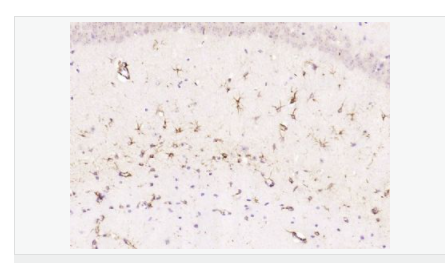

| 產(chǎn)品介紹 | This gene encodes one of the major intermediate filament proteins of mature astrocytes. It is used as a marker to distinguish astrocytes from other glial cells during development. Mutations in this gene cause Alexander disease, a rare disorder of astrocytes in the central nervous system. Alternative splicing results in multiple transcript variants encoding distinct isoforms. [provided by RefSeq, Oct 2008] Function: GFAP, a class-III intermediate filament, is a cell-specific marker that, during the development of the central nervous system, distinguishes astrocytes from other glial cells. Subunit: Interacts with SYNM. Isoform 3 interacts with PSEN1 (via N-terminus). Subcellular Location: Cytoplasm. Note=Associated with intermediate filaments. Tissue Specificity: Expressed in cells lacking fibronectin. Post-translational modifications: Phosphorylated by PKN1. DISEASE: Defects in GFAP are a cause of Alexander disease (ALEXD) [MIM:203450]. Alexander disease is a rare disorder of the central nervous system. It is a progressive leukoencephalopathy whose hallmark is the widespread accumulation of Rosenthal fibers which are cytoplasmic inclusions in astrocytes. The most common form affects infants and young children, and is characterized by progressive failure of central myelination, usually leading to death usually within the first decade. Infants with Alexander disease develop a leukoencephalopathy with macrocephaly, seizures, and psychomotor retardation. Patients with juvenile or adult forms typically experience ataxia, bulbar signs and spasticity, and a more slowly progressive course. Similarity: Belongs to the intermediate filament family. SWISS: P14136 Gene ID: 2670 Database links: Entrez Gene: 2670 Human Entrez Gene: 14580 Mouse Omim: 137780 Human SwissProt: P14136 Human SwissProt: P03995 Mouse Important Note: This product as supplied is intended for research use only, not for use in human, therapeutic or diagnostic applications. 星形膠質(zhì)細胞標志物 (Astrocyte Marker) GFAP是一個(gè)56kDa的中間絲蛋白(intermediate filament,IF),在中樞神經(jīng)系統發(fā)育期是一個(gè)特異性的標志物,以區別星形細胞和其它膠質(zhì)細胞。GFAP表達在皮層和海馬,急、慢性皮質(zhì)酮治療時(shí)表達減少。 GFAP可以和人、大鼠、小鼠的GFAP反應,在正常和腫瘤性的星形膠質(zhì)細胞陽(yáng)性表達,而神經(jīng)節細胞、神經(jīng)元、成纖維細胞、少突膠質(zhì)細胞和這些細胞來(lái)源的腫瘤細胞陰性表達,主要用于星形膠質(zhì)瘤等中樞神經(jīng)系統腫瘤的診斷和鑒別診斷,GFAP的缺乏可導致AD病。 |